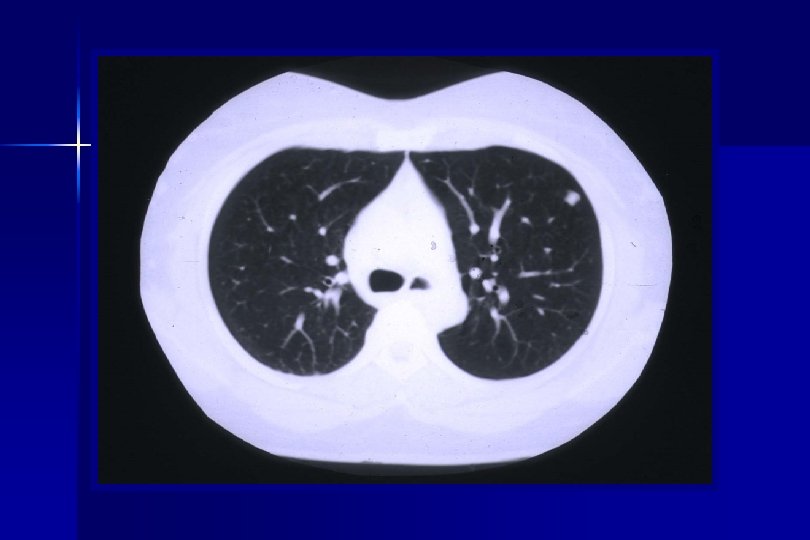

Eligibility Criteria Part I: Pre-Operative Criteria (Pre-Registration/Randomization): ● Patients must have a suspicious lung nodule for clinical Stage I NSCLC. ● Patient must have a mass ≤ 3 cm maximum diameter by CT size estimate: Clinical stage Ia or selected Ib (i. e. , with visceral pleural involvement. ● Patient must have a CT scan of the chest with upper abdomen within 60 days prior to date of pre-registration.